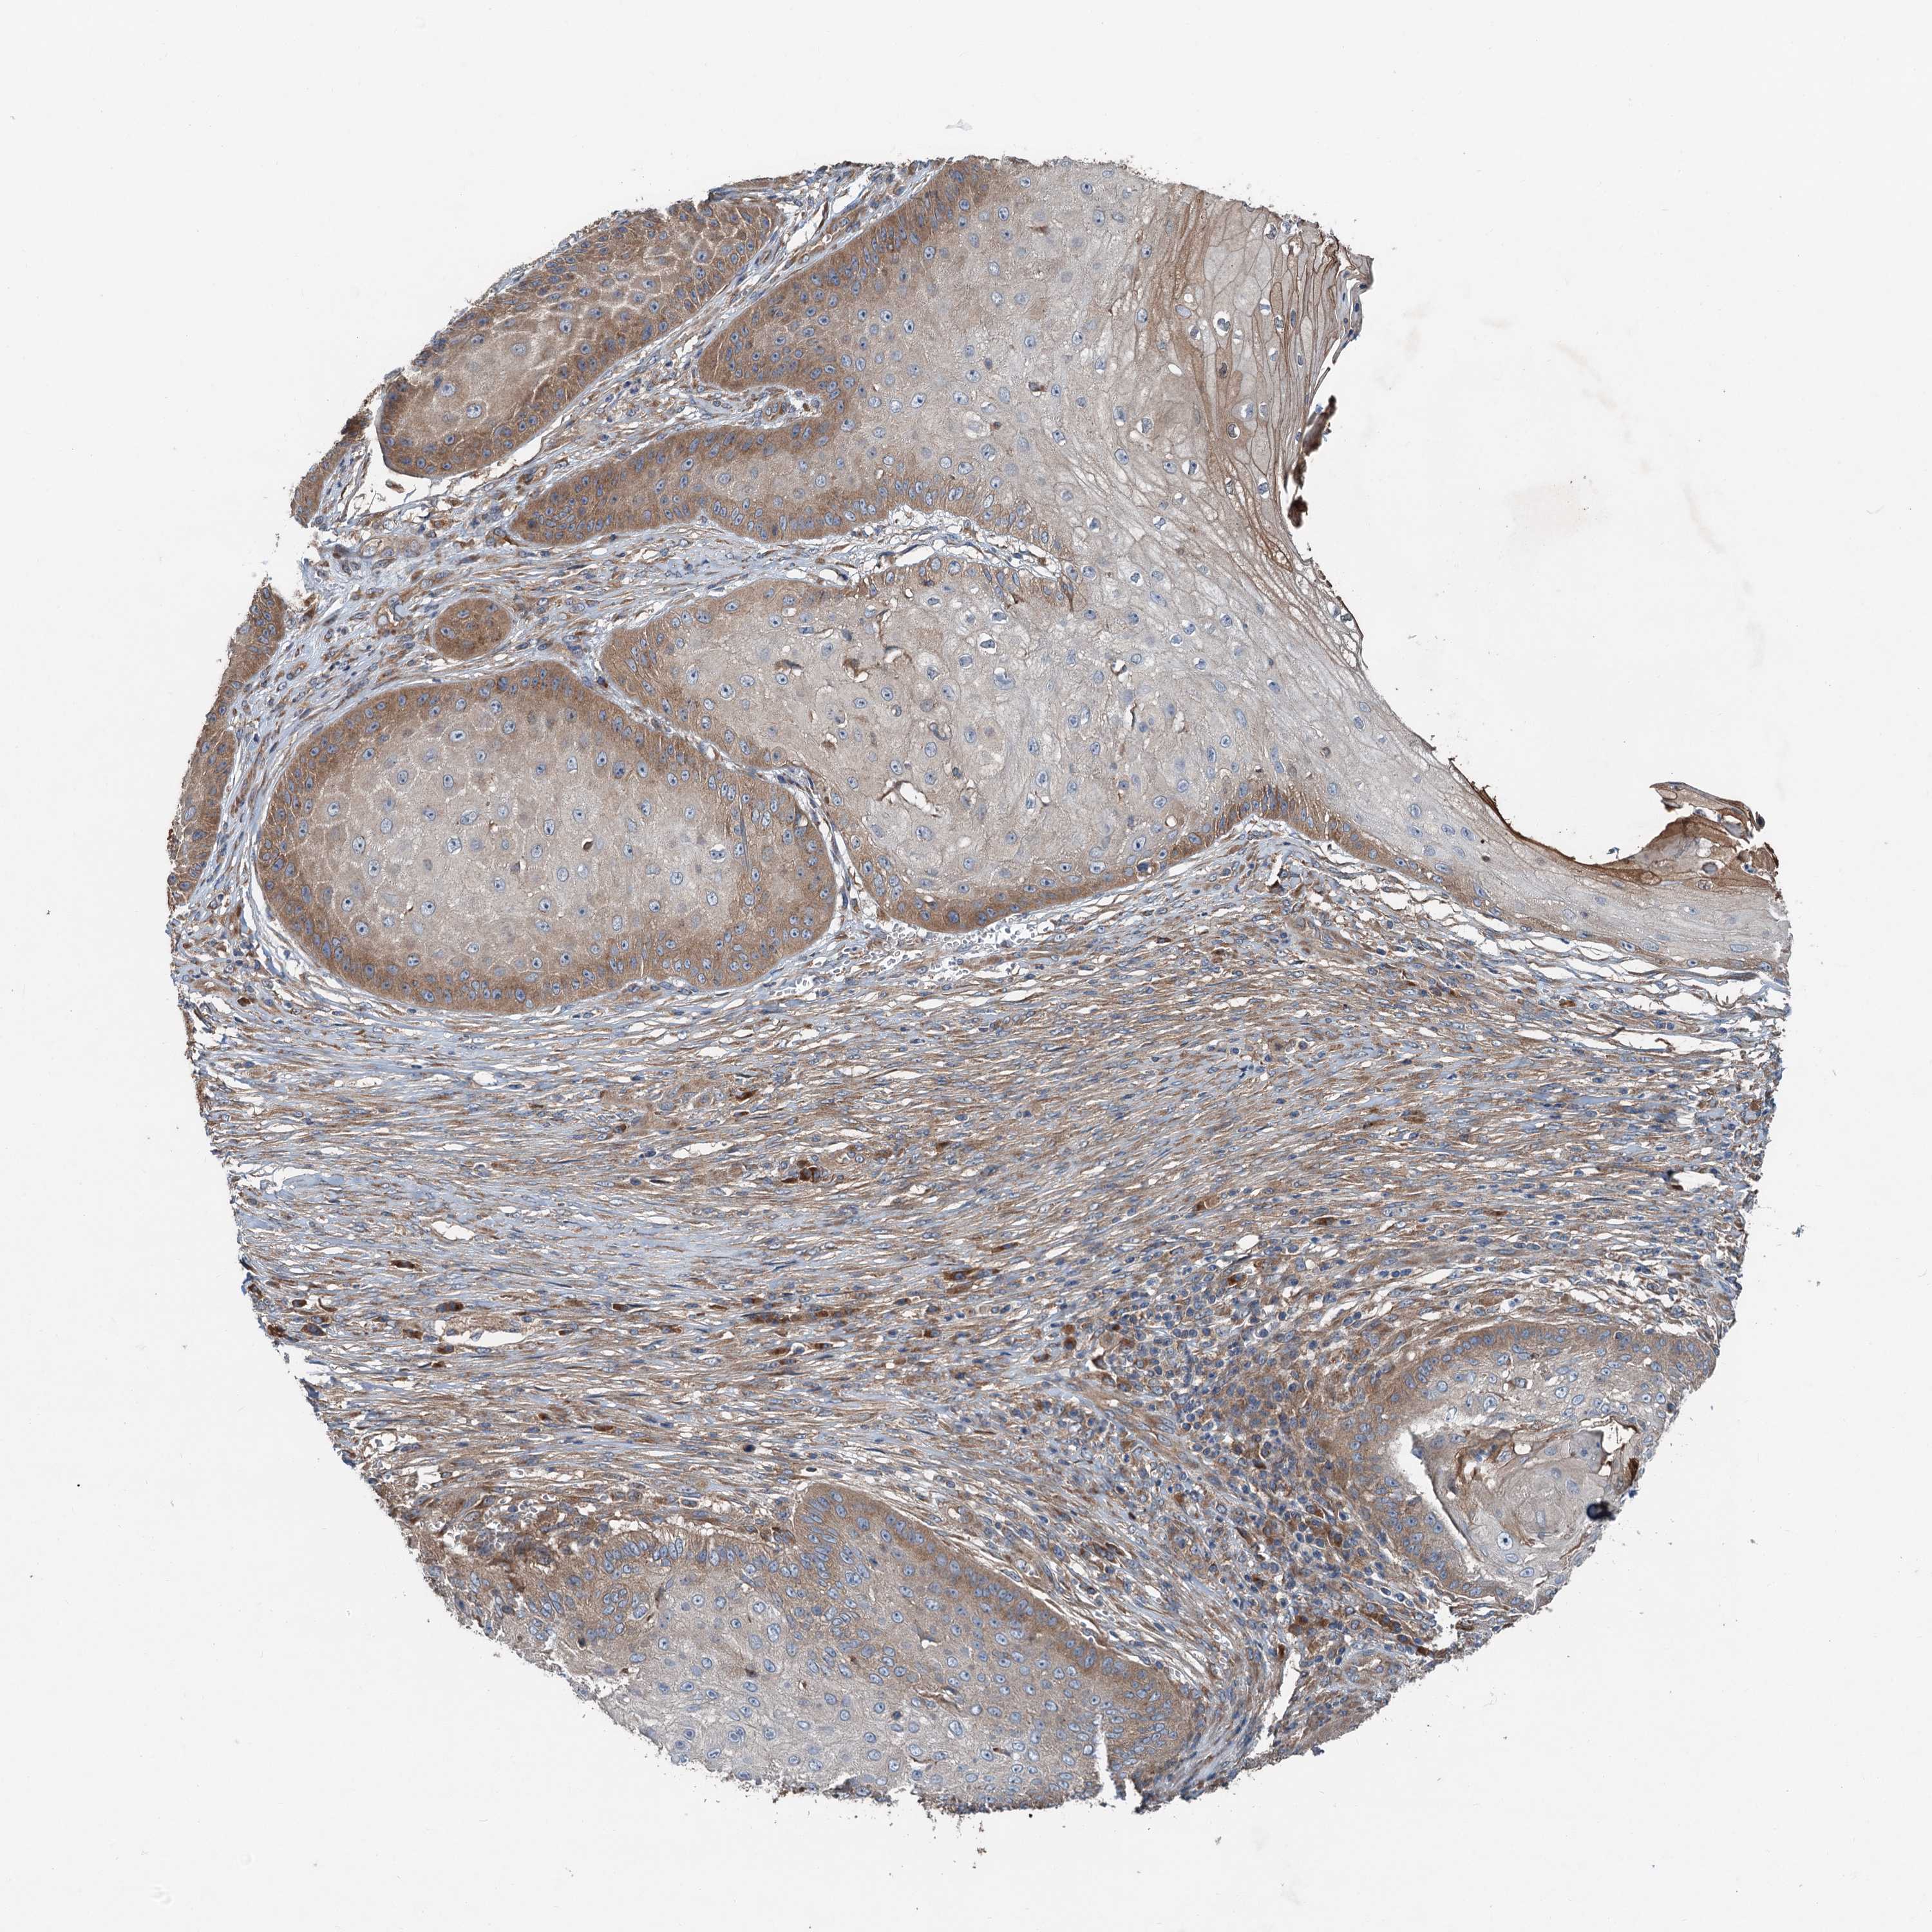

Basal cell and squamous cell cancer

SKIN CANCER - Protein expressioni

A mouse-over function shows sample information and annotation data. Click on an image to view it in a full screen mode. Samples can be filtered based on level of antibody staining by selecting one or several of the following categories: high, medium, low and not detected. The assay and annotation is described here.

Antibody stainingi

Antibody staining in the annotated cell types in the current human tissue is reported as not detected, low, medium, or high, based on conventional immunohistochemistry profiling in selected tissues. This score is based on the combination of the staining intensity and fraction of stained cells.

Each image is clickable and will lead to virtual microscopy that enables deeper exploration of all samples and also displays staining intensity scores, fraction scores and subcellular localization as well as patient and tissue information for each sample.

Antibody HPA040353

Staining

High

Intensity

Strong

Quantity

>75%

Location

Nuclear

Basal cell carcinoma